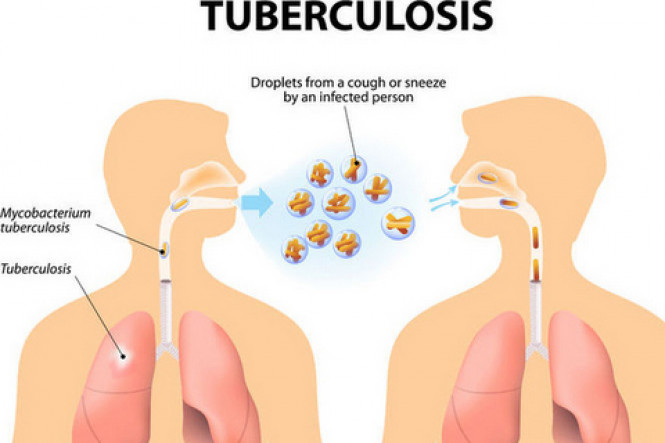

Respiratory diseases

Respiratory diseases are conditions that affect any of the processes involved with breathing. If you or someone you know are one of the 1 in 6 New Zealanders that lives with a respiratory condition, here you can find some useful information on how to manage the condition well.